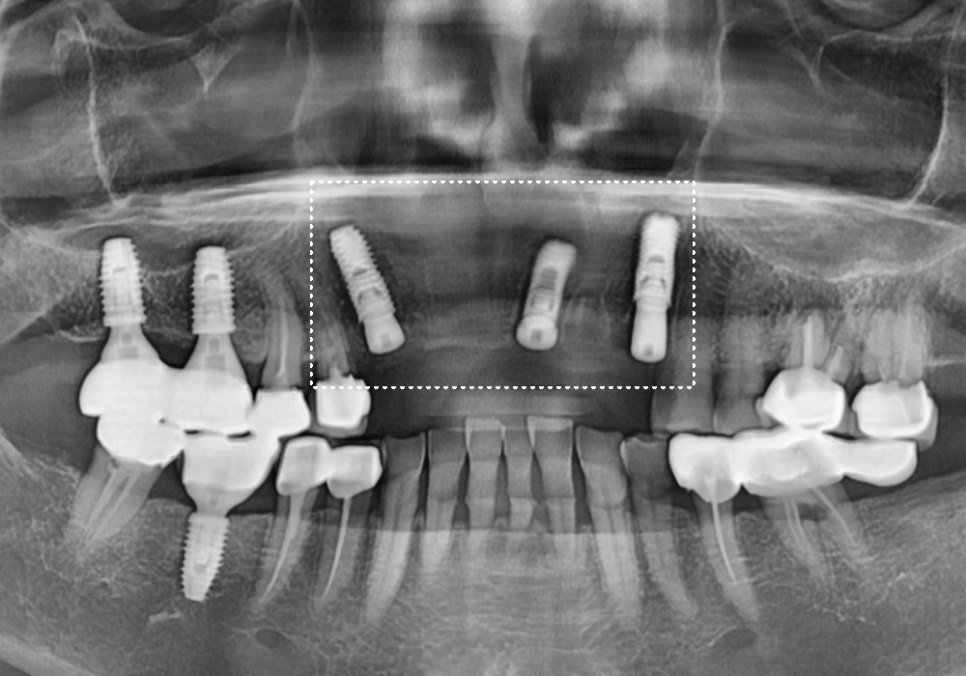

입안을 살펴보니 앞니 6개가 (#13~23)

브릿지로 연결된 상태였는데,

보철물과 잇몸 경계 사이로

고름이 계속 배어 나오고 있었어요.

방사선 사진과 CT를 확인해보니

오래된 보철물 안쪽으로

2차 충치가 심하게 진행되어 있었고,

240315

특히 왼쪽 송곳니(#23)는 이미 치아 머리 부분이

부러져 뿌리와 분리된 상태였습니다.

뿌리 끝까지 염증이 퍼져

잇몸뼈가 많이 녹아있었기에,

안타깝게도 발치를 진행하기로 했습니다.